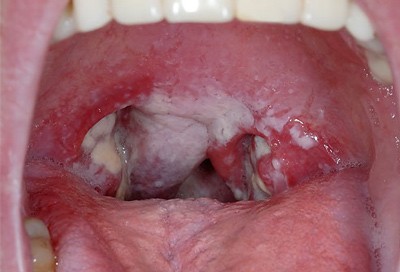

Sưng hạch hầu và có những mảng trắng trong cổ họng hoặc những chấm đỏ nhỏ có thể xuất hiện trên vòm miệng;